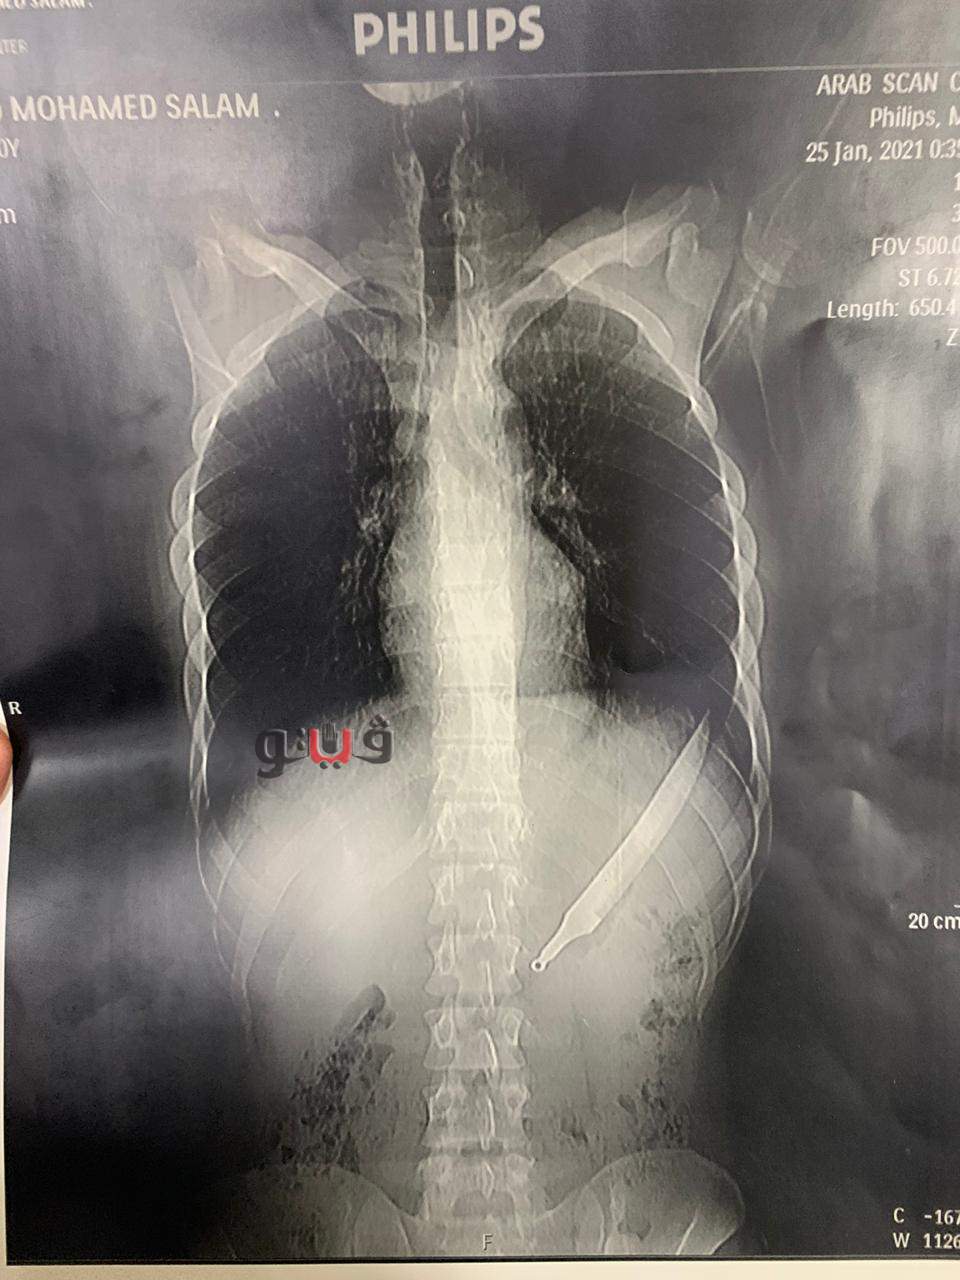

أعلن الدكتور سعد مكي، وكيل وزارة الصحة بالدقهلية، عن نجاح فريق طبي في إنقاذ حياة مريض ابتلع سكين مطبخ كبير، حيث حضر المريض للمستشفى الدولي يعاني من آلام شديدة بالبطن.

وبعمل الأشعات والفحوصات تبين وجود جسم غريب، وتمكن الفريق الطبي من إجراء عملية جراحية لاستخراج الجسم الغريب (سكين مطبخ)، وتكللت العملية بالنجاح وخرج المريض بحالة مستقرة.